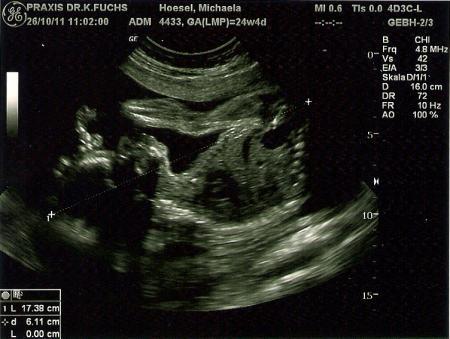

Hallöchen Mädels. Ich war heute wieder beim FA und unserem kleinen Mann gehts bestens. Die Ärztin ist super zufrieden mit Mama und Sohn. Ich bringe nun 6kilo mehr auf die Waage, aber das ist halb so schlimm. Ich kanns vertragen.^^ Der Kleine wiegt jetzt um die 660gramm und ist zwischen 30-35cm groß. Bin heute 24+4 und finde seine größe schon riesig. Ich befürchte das der Kleine voll und ganz nach seinem Vater kommt und demnach auch früher kommt. Meine FÄ meinte das man das net sagen könnte und einfach abwarten. Mein Freund kam damals 5Wochen zu früh und war schon 50cm groß zu seiner Geburt. Hab auch 4 tolle Bilder bekommen und eins muss ich dem kleinen lassen.... er ist ganz schön gelenkig. :D Das ganze hat mich zwar 30Eus gekostet, aber das war es uns wert. Wollten die Entwicklung unseres Sohnes auch auf Bildern festgehalten haben. Wünsch euch einen tollen Abend und hänge jetzt alle 4 Bilder ran, sofern es möglich ist.^^ LG, Michaela

Man sieht nochmal die Gesichtskonturen und eine Hand, sowie einen leicht verdrehten fuß. Ist aber in Ordnung sagt die FÄ.